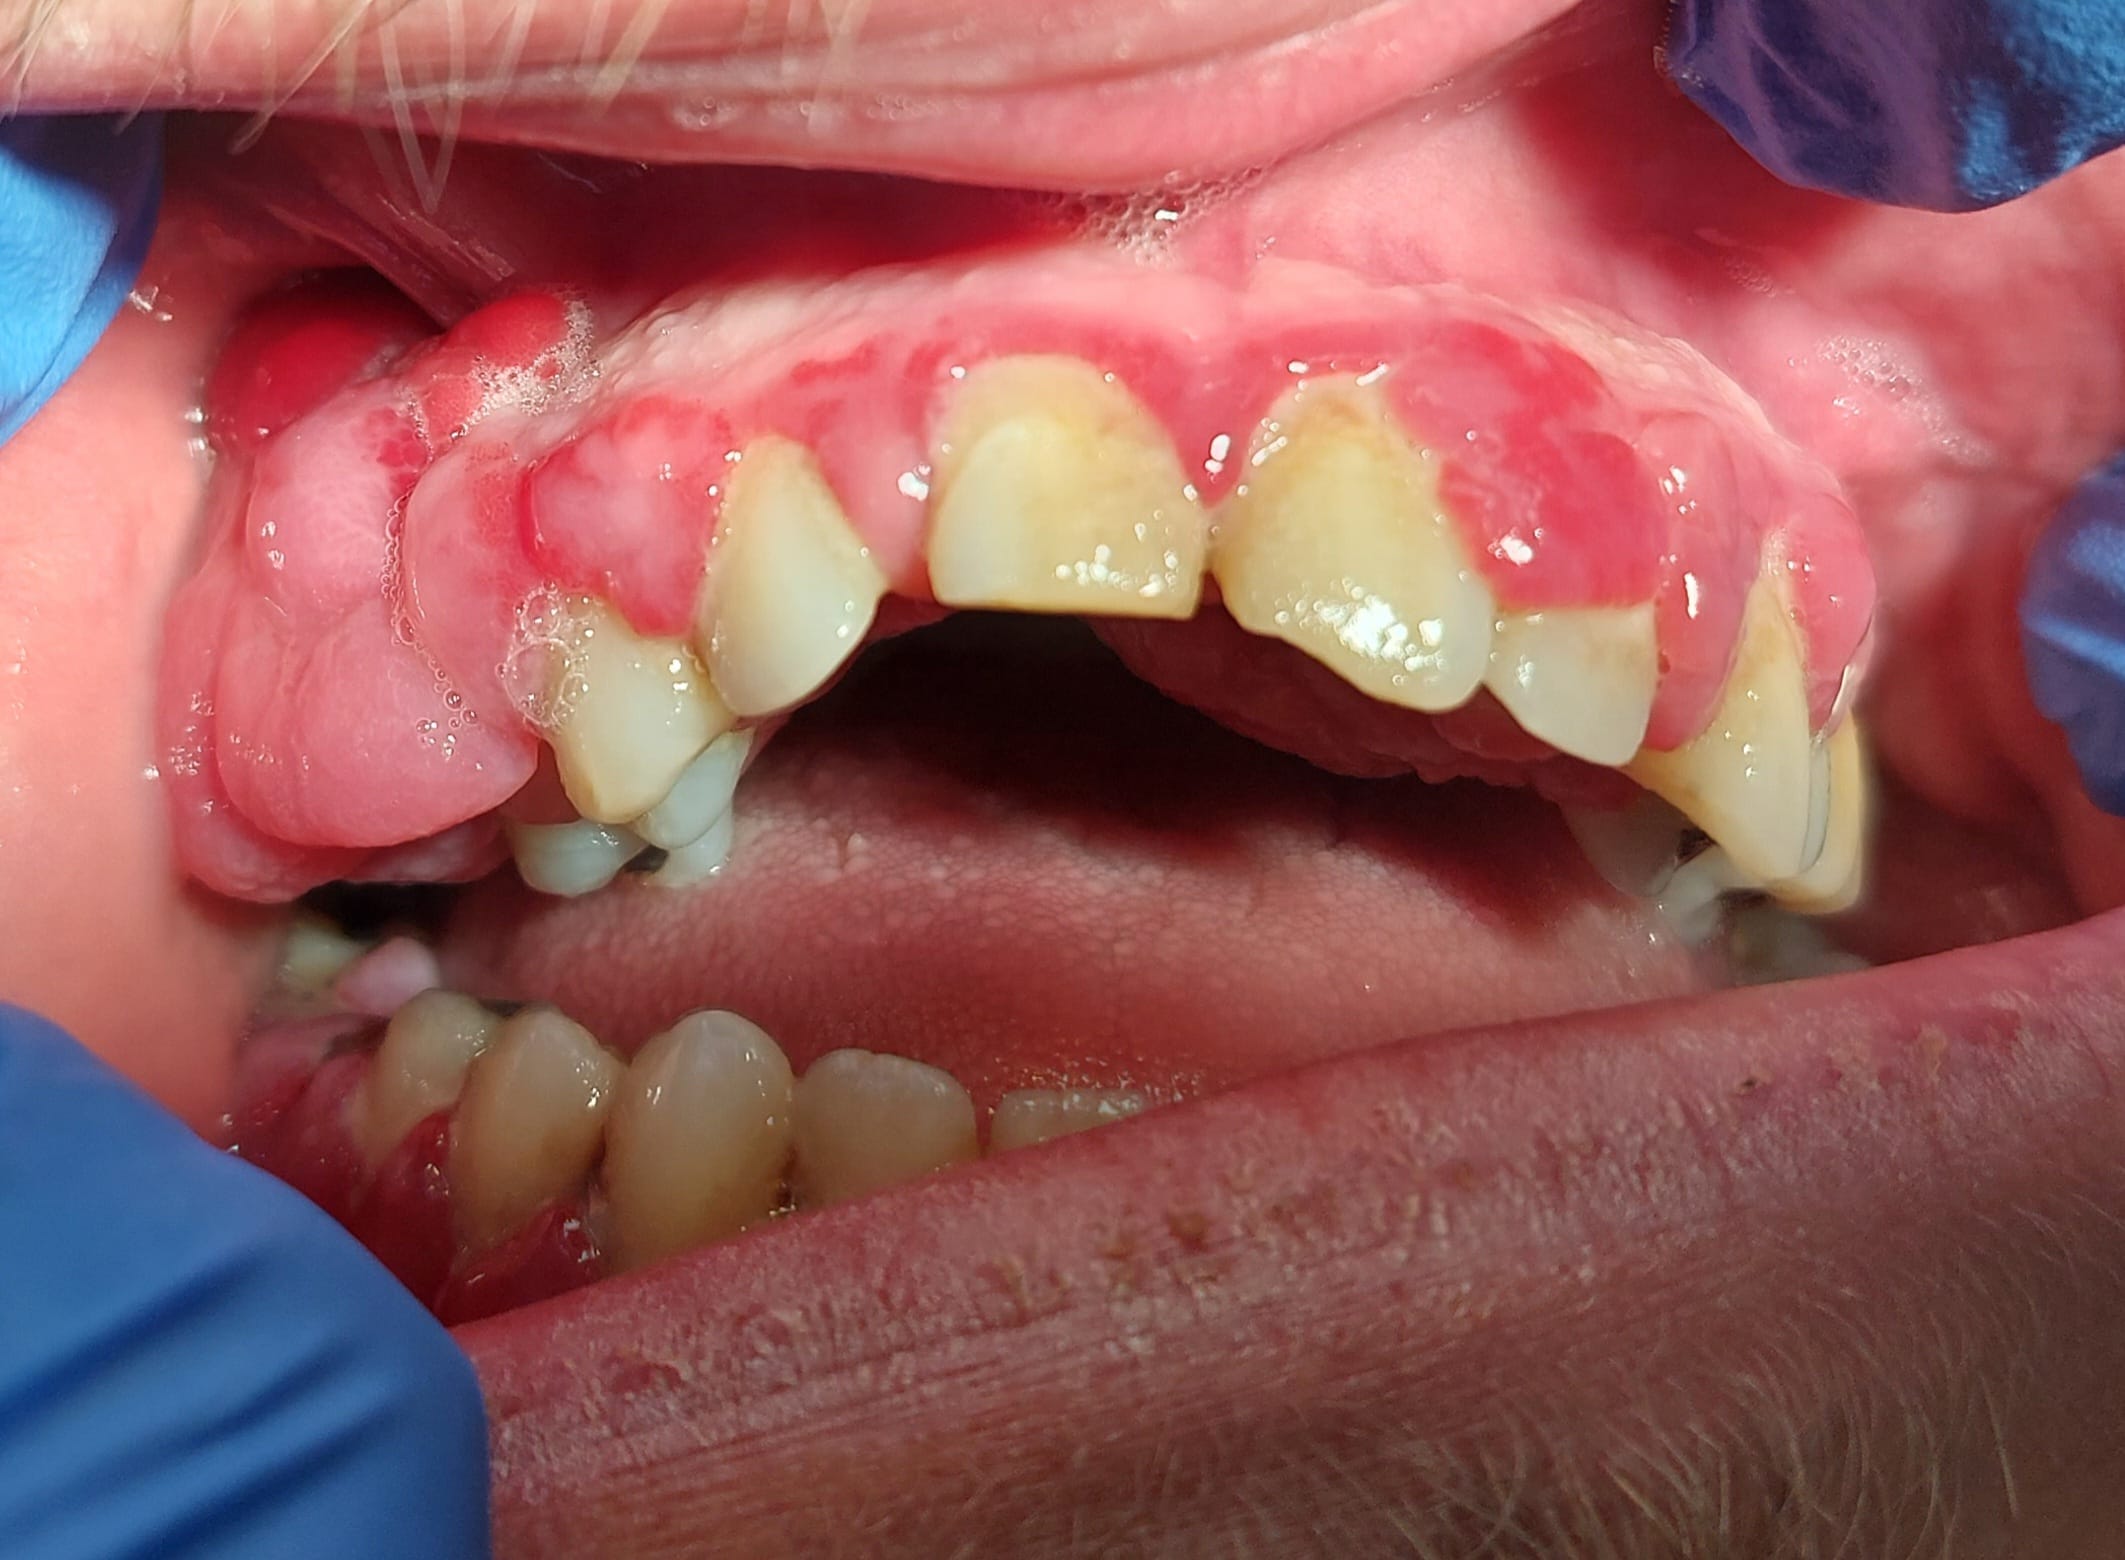

Patient de 31 ans, hépatite B depuis 1995 traitée par baraclude, à priori sans soucis mais pas de prise de sang depuis 6 mois. Également léger retard mental du à un syndrome lié à l'X.

Consulte pour hyperplasie gingivale apparue progressivement en 5 mois (RAS avant d'après lui), totalement indolores, pas de saignement sauf en insistant aux collets en gingivite.

Brossage intense du patient mais technique perfectible (cf photos).

Les 2 principales zones hyperplasiques dans le vestibule secteur 10 et palatin secteur 20 sont bien pédiculées et mobiles.

Voilà les photos.